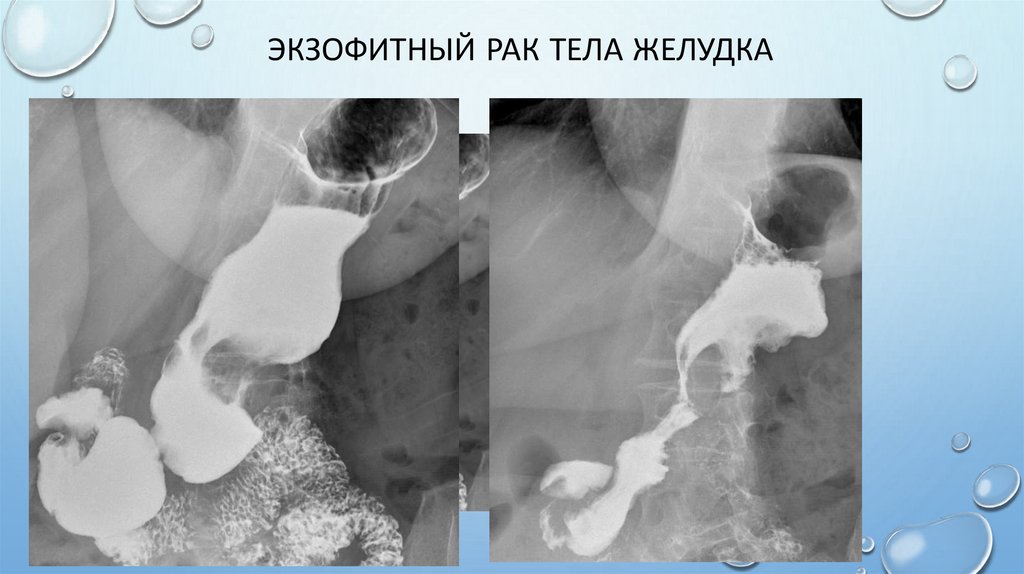

Экзофитный рак тела желудка

68. Экзофитный рак тела желудка

ЭКЗОФИТНЫЙ РАК:

RN-СИМПТОМЫ

• ДЕФЕКТ НАПОЛНЕНИЯ (ЦЕНТРАЛЬНЫЙ ИЛИ КРАЕВОЙ) НЕПРАВИЛЬНО

ОКРУГЛОЙ ФОРМЫ С НЕРОВНЫМИ, БУГРИСТЫМИ КОНТУРАМИ;

• ДЕФЕКТ ГЛУБОКО ВДАЕТСЯ В ПРОСВЕТ ЖЕЛУДКА;

• АТИПИЧНЫЙ РЕЛЬЕФ: МНОЖЕСТВЕННЫЕ ДЕФЕКТЫ НА РЕЛЬЕФЕ С

НЕЧЕТКИМИ КОНТУРАМИ, РАЗДЕЛЕННЫЕ РАЗЛИЧНОЙ ШИРИНЫ ПОЛОСКАМИ

БАРИЕВОЙ ВЗВЕСИ;

• ПОСТОЯНСТВО РЕЛЬЕФА: ОТСУТСТВИЕ ЕГО ИЗМЕНЧИВОСТИ В ПРОЦЕССЕ

ИССЛЕДОВАНИЯ ПРИ КОМПРЕССИИ И ПАЛЬПАЦИИ;

• ОБРЫВ СКЛАДОК НА ГРАНИЦЕ С ОПУХОЛЬЮ;

• ОТСУТСТВИЕ ПЕРИСТАЛЬТИКИ В ОБЛАСТИ ПОРАЖЕНИЯ;

• СИМПТОМ «ОБРУЧА» - ТОНКАЯ ПОЛОСКА БАРИЯ, ОКАЙМЛЯЮЩАЯ ОПУХОЛЬ,

ПОСЛЕ ЧАСТИЧНОЙ ЭВАКУАЦИИ БАРИЯ.